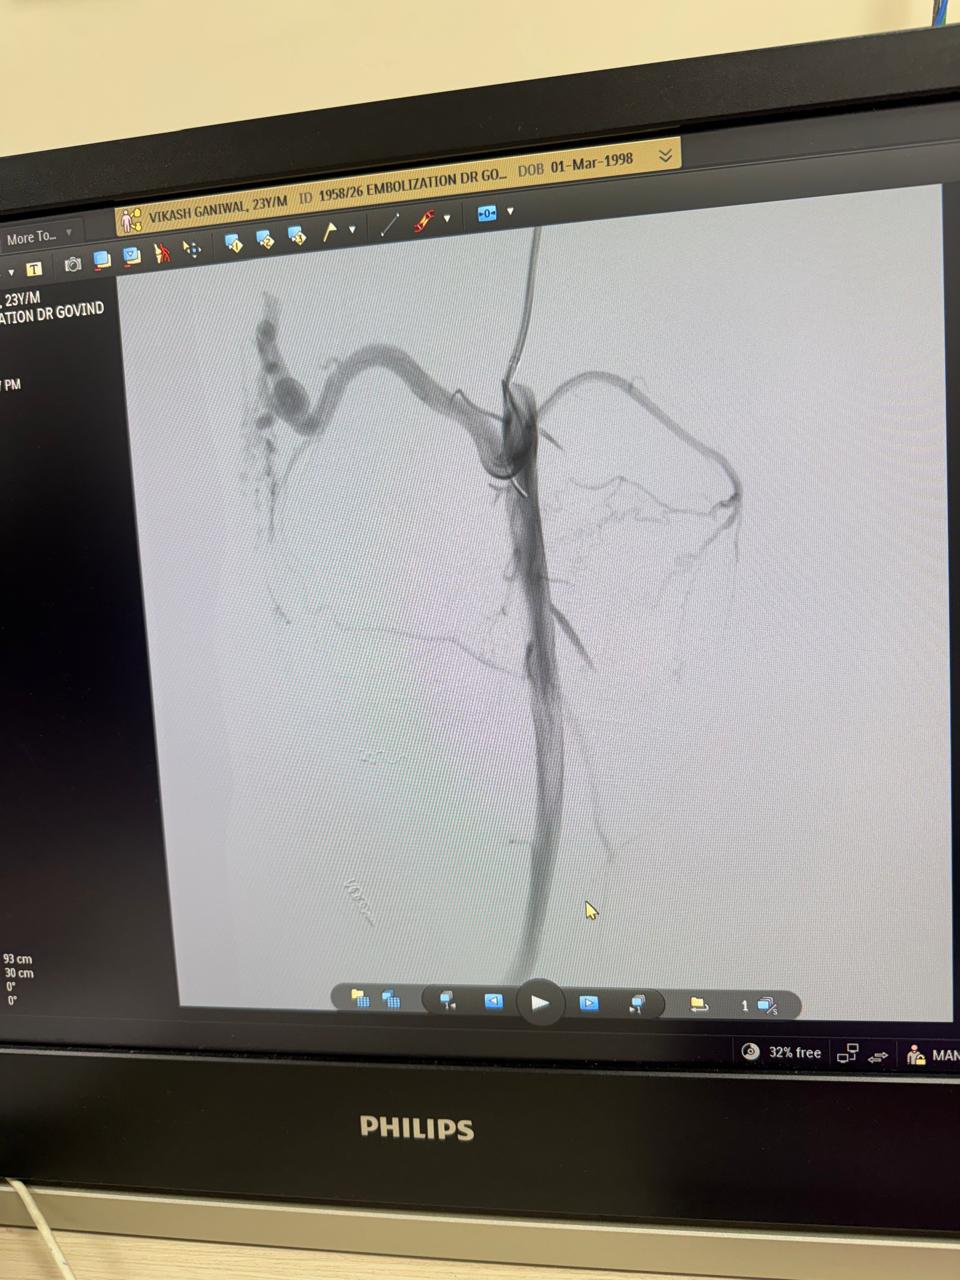

Vascular embolization of arteriovenous malformation